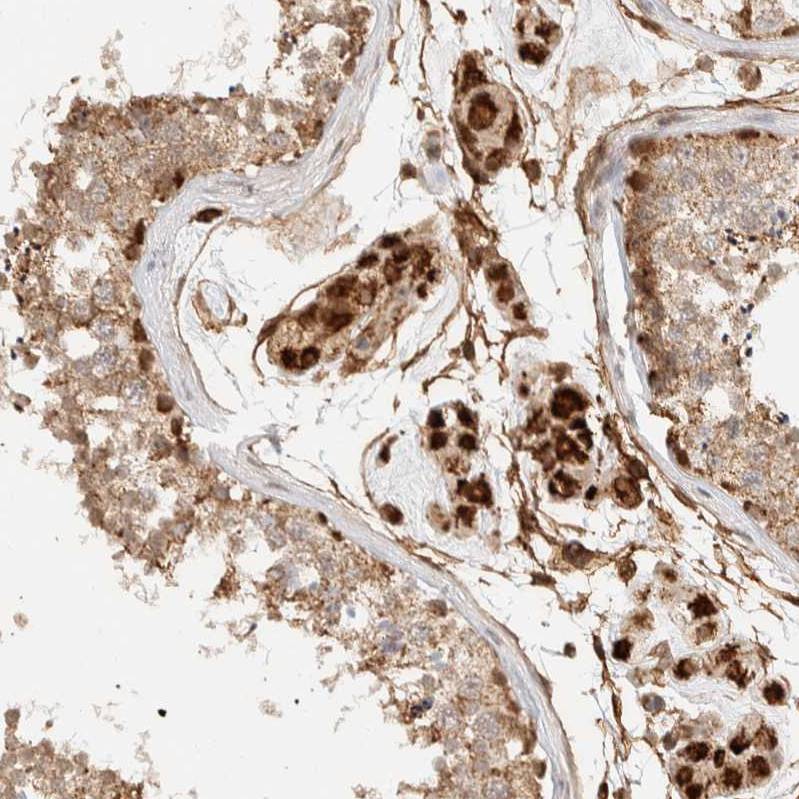

Immunohistochemical staining of human testis shows strong cytoplasmic positivity in Leydig cells and cells in seminiferous ducts.